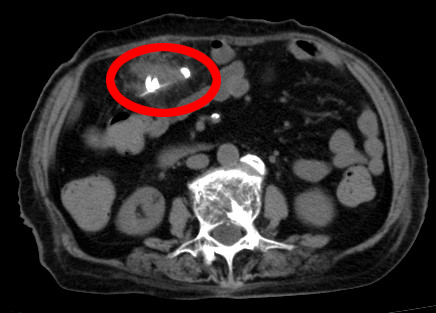

家住花桥镇的冯奶奶,今年98岁,肚子疼得厉害伴有发热,至当地医院就诊,腹部CT考虑腹腔脓肿,腹腔异物;在当地医院行腹腔脓肿穿刺引流术,症状好转,但腹痛伴发热仍反复发作。

情况危急,由于肠穿孔时间较久,已经并发了严重的腹腔脓肿,征求了患者同意后,昆山市中医医院外一科顾卯林团队立刻与麻醉科为冯奶奶确定了手术方案——开腹探查+结肠修补术。

层层剥茧, 终于,一根扎穿破横结肠的鱼刺暴露出来,仔细取出鱼刺后,吸尽腹腔内的脓液,又彻底冲洗腹腔,并行结肠修补术。术后冯奶奶安全度过了感染关、伤口愈合关,十天后顺利出院。